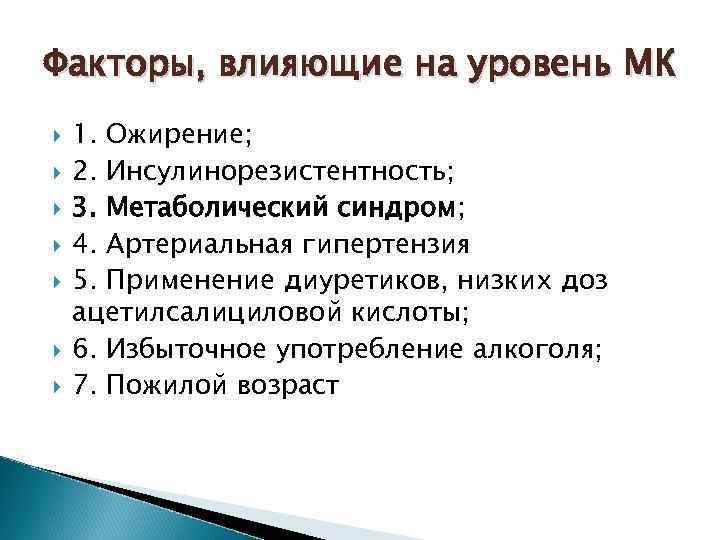

Факторы, влияющие на уровень МК 1. Ожирение; 2. Инсулинорезистентность; 3. Метаболический синдром; 4. Артериальная гипертензия 5. Применение диуретиков, низких доз ацетилсалициловой кислоты; 6. Избыточное употребление алкоголя; 7. Пожилой возраст